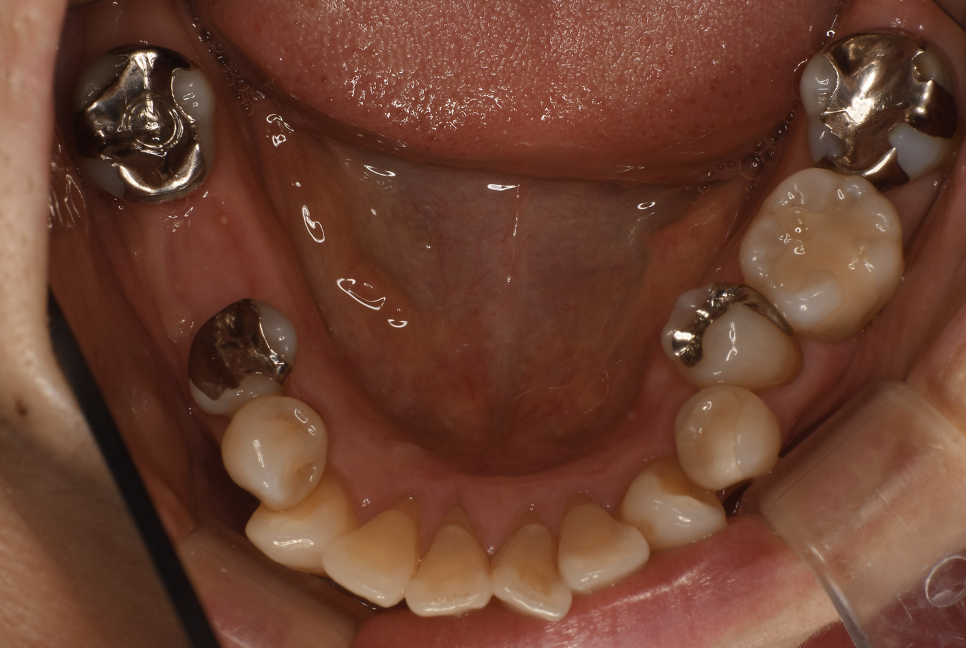

Before

| 備考 | 院長より 残念ながら保存できなかった銀歯を抜歯して、インプラントを埋入しました。インプラント(人工歯根)と被せ(フルジルコニアCr)はネジで連結してあり必要に応じて外してチェックできるようになっています。写真ではメンテナンス時でネジ穴が見える状態になっています。 通常はネジ穴はプラスティックで蓋をして見えない状態になっています。 |